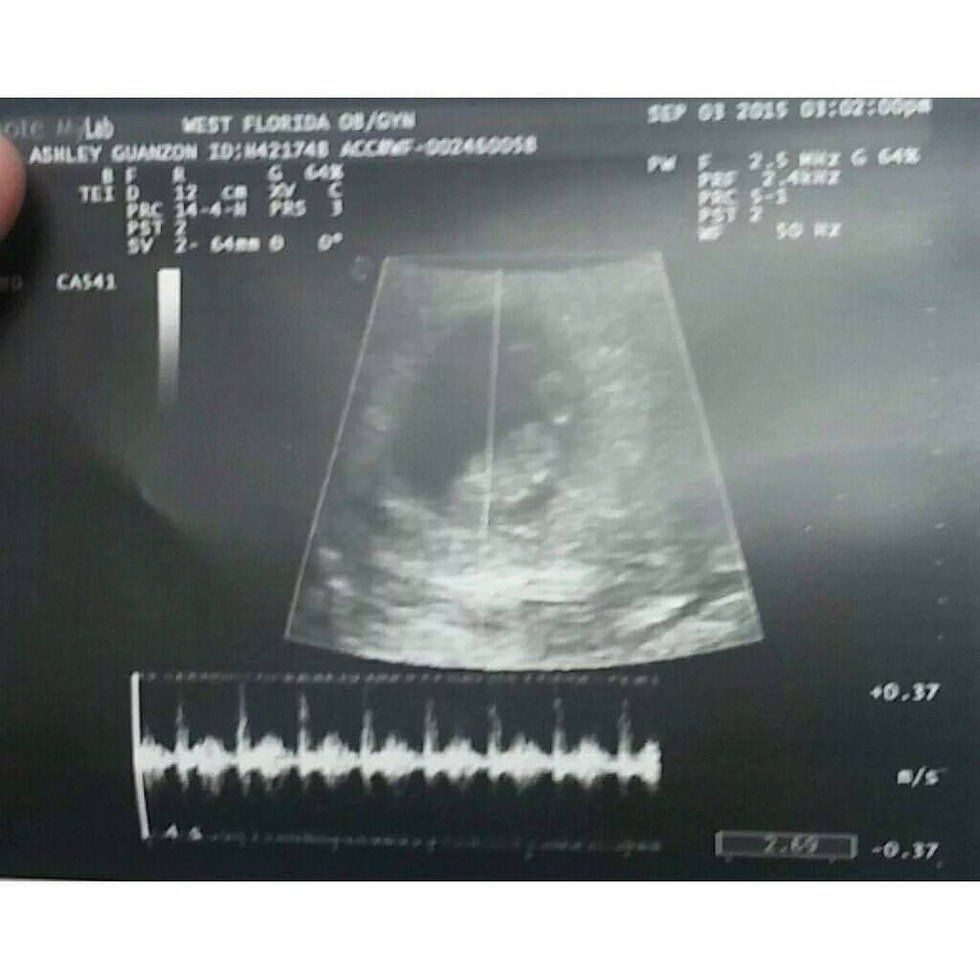

It took one appointment, one procedure for your life to change and it happens so fast you honestly forget to breathe. September 24th, 2015- I was going to my 12-week appointment, fingers crossed that we could find out the sex of the baby. Instead, it was a regular check up appointment and I guess that was okay. After I told the good doctor that everything had been pretty good, minus the unexplained bleeding (side-note, during the pregnancy I had vaginal bleeding about 3 times, 3 separate days. I went to the ER and each time I went I was told there was nothing wrong.)- she brought out her Doppler (an instrument used to hear baby's heartbeat) and proceeded to search for my angel's heart. She sort of struggled, she explain that since I just hit 12 weeks that it could still be difficult to find, so she moved me to ultrasound. The ultrasound tech wasn't so reassuring, she was silent the whole entire time. And all we could see were just. Blobs. In that moment- I knew there was something really, really wrong. I was brought back into my room. The doctor walks in and I see the ultrasound picture in hand--I see in white letters "no fetal heartbeat" and before she even said a word...I was absolutely silent. She looks at me with the most miserable look and all she needed to say was "I'm so sorry" and.. I lost it. I must've been in my room for a good while because people were staring at me. I didn't care--I cried my ass all the way to my car. I called her dad, he was so anxious to know if we found out what the sex was, but all I could say is "she's not there" and immediately I drove out to Santa Rosa Beach and we mourned together. August 25th, 2015, my water broke. I ran to the bathroom and not to be gross but...nothing but blood everywhere. As soon as he got home, I rushed to the ER. I was admitted pretty much immediately, come to find out I had a fever of 108 and surprise--I was going into labor. I was screaming so loud they had to give me morphine because I could not stop screaming. What was I suppose to do? I don't know what hurt more, my contractions or the fact I know that my body is trying to birth out a dead baby. One thing led to another and I was taken to OR and when I woke up. I wished I hadn't.